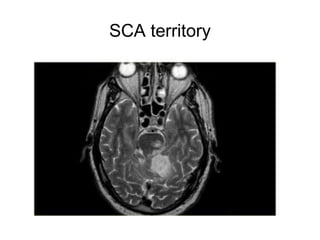

SCA territory